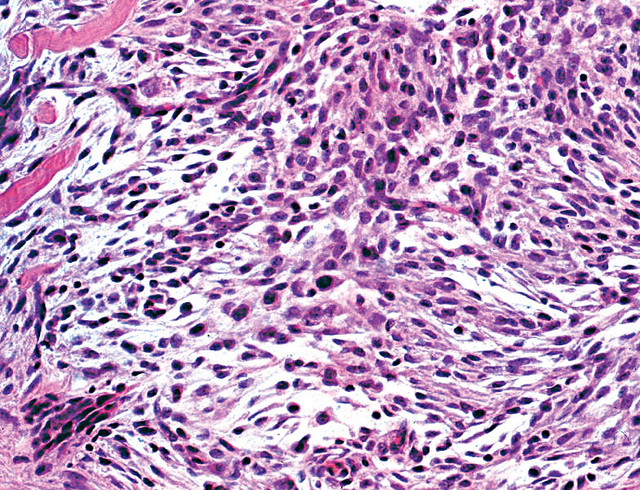

Microscopic (histologic) description

- Cellular, myxoid or mixed subtypes

- Involves dermis or subcutis

- Multinodular mass with myxoid matrix and peripheral fibrosis

- Whorled or focally fascicular patterns of spindled and epithelioid mononuclear cells with abundant cytoplasm, indistinct cell borders

- Margins usually positive; usually occasional multinucleated giant cells

- Variable nuclear atypia

- Median 4 MF / 25 HPF, may have 10+ MF / 25 HPF, may be atypical

Microscopic (histologic) images